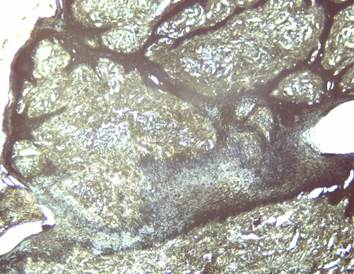

Los hallazgos histoquímicos con la coloración de EVG corresponden con los reportados en la literatura, para el diagnóstico del papiloma, siendo las papilas epidérmicas, la hiperplasia epitelial y la acantosis el hallazgo más común coincidiendo con Iglesias & Batista (2003); Monteiro et al. (2008); Vázquez et al. (2012). Analizando las características clínicas del papiloma, se avinieron con los hallazgos histopatológicos encontrados en todas las muestras estudiadas, constituyendo un aporte importante para el diagnóstico de esta condición patológica (Figura 2).

Figura 2. Hiperplasia epitelial y acantosis con proyecciones hacia la dermis e hiperqueratosis. Las fibras colágenas se observan en gris oscuro, los fibroblastos en azul. Coloración EVG 10X.

Elaboración: Los autores.